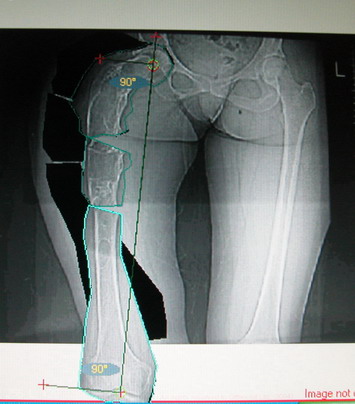

Возможна аппаратная коррекция оси с формированием клиновидного регенерата, которая решила бы и проблему укорочения (что, впрочем, нужно уточнить по схеме, сделанной по рентгенограмме с хорошим захватом смежных суставов - схемка по присланному снимку в приложении). По окончании коррекции - блокируемый стержень, который и сократит время пребывания в аппарате, и вообще возврата к нормальной жизни, а также будет мерой профилактики патологических переломов.

А может быть, если при планировании выяснится, что "открытый клин" решает все проблемы, и есть достаточное приведение в тазобедренном суставе, пойти на одномоментную операцию - чрескожная поперечная остеотомия на вершине деформации и закрытый интрамедуллярный остеосинтез.

Собственно сустав не беспокоит, объем движений полный. По скиаграммам получается, что достаточно одной остеотомии на вершине деформации, чтобы восстановить длину и вывести коленный сустав в нужное положение.

Т.к. укорочение 7 см, то начинать будем с соеотомии и коррекции аппаратом. Спасибо

Моё мнение, что двойная остеотомия бедра с аппаратом Илизарова + Гексаподный механизм, или Тэйлора, В данной ситуации является методом выбора. Я очень извеняюсь за качество прилагаемых снимков, в которых я постарался отразить разницу междe одной и двумя остеотомиями бедра.